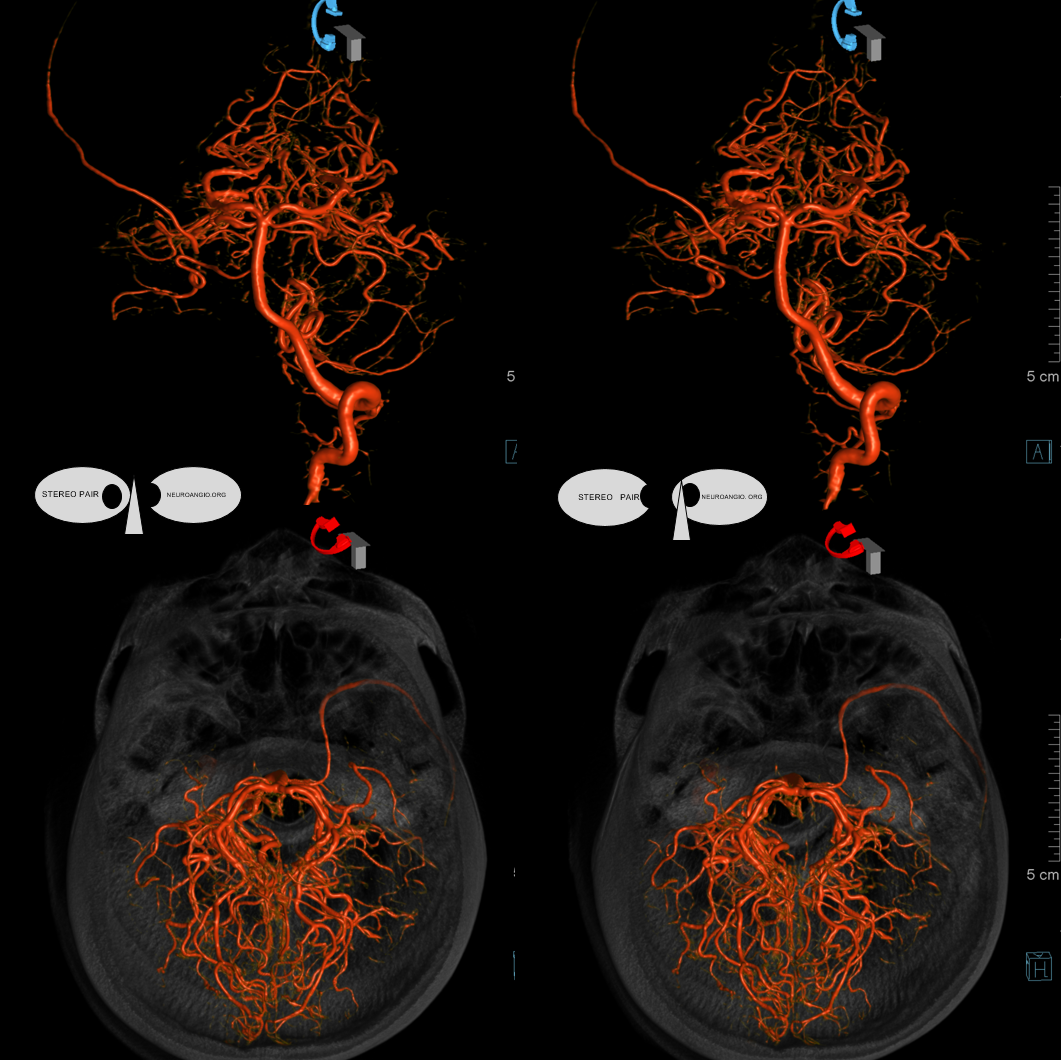

And, in case you really dont believe its the trigeminal artery, check out these co-registration images of angio (axial MIP reconstructions of rotational angio) and finally with superimposed tractography of the Vth nerve! Images courtesy Dr. Nader Delavari

Superimposed MRI and angio axials (our trigeminal artery is shown bi arrow)

Now with tractography of CN V